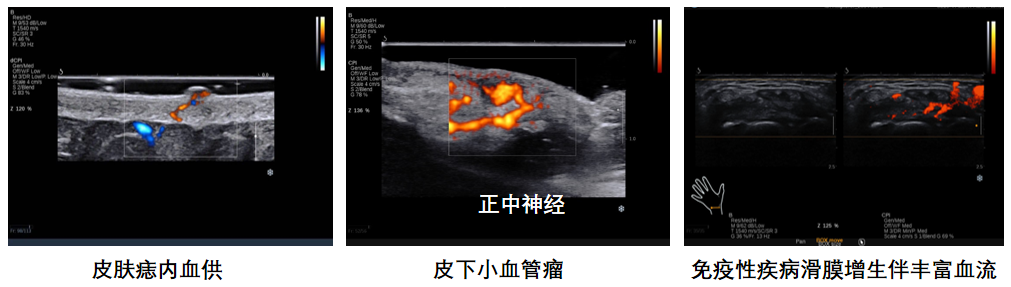

平面波超微细血流显像

彩色多普勒成像、3D壁滤波原理

血流敏感度明显提升,分辨率达微米级别

支持灰阶和微血流量同步测量、可测极低速血流的速度

多种模式,多数据定量评估。

74f501571ed455f9a4eebb1b8e37b73.png